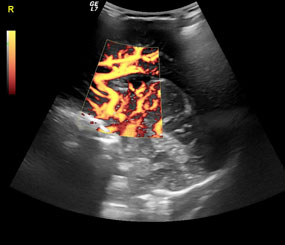

Tο ιατρείο μας παρέχει πλέον τη δυνατότητα εκτέλεσης κατ’ Οίκον όλων των εξετάσεων υπερηχογραφημάτων και triplex αγγείων. Με την καινούρια, φορητή και υπερσύγχρονη μονάδα υπερήχων NextGen LOGIQ e, General Electric (τελευταίας γενιάς) παρέχουμε την δυνατότητα για άμεσες λύσεις σε διαγνωστικά προβλήματα ακόμα και σε ασθενείς που δεν έχουν δυνατότητα μετακίνησης. Έτσι ο ασθενής και η οικογένειά του αποφεύγουν την ταλαιπωρία διακομιδής του σε νοσοκομεία ή διαγνωστικά κέντρα. Οι φορητοί υπερηχογράφοι μπορούν πλέον να εκτελέσουν όλες τις εξετάσεις, με τη βασική προϋπόθεση να είναι σύγχρονης κατασκευής. Η απουσία ακτινοβολίας και ο εύχρηστος τρόπος χρήσης καθιστούν την εξέταση πολύ προσιτή.